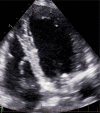

Conduction system pacing (CSP) has emerged as a more physiological alternative to right ventricular pacing and is also being used in selected cases for cardiac resynchronization therapy. His bundle pacing was first introduced over two decades ago and its use has risen over the last five years with the advent of tools which have facilitated implantation. Left bundle branch area pacing is more recent but its adoption is growing fast due to a wider target area and excellent electrical parameters. Nevertheless, as with any intervention, proper technique is a prerequisite for safe and effective delivery of therapy. This document aims to standardize the procedure and to provide a framework for physicians who wish to start CSP implantation, or who wish to improve their technique.